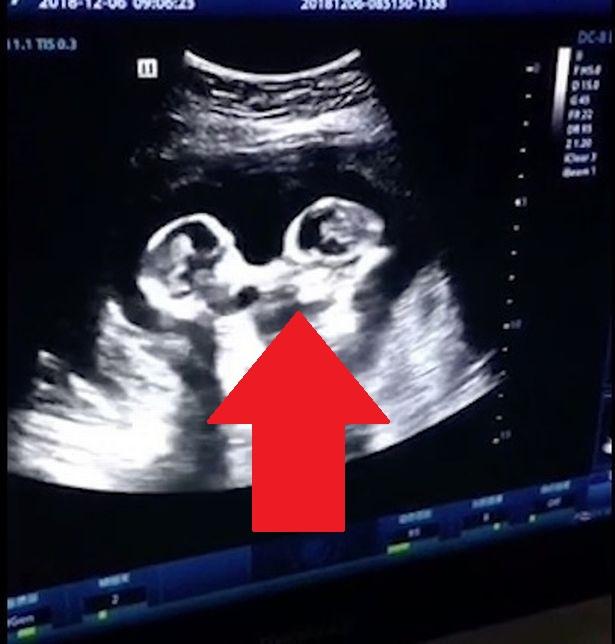

Un caz la 4,7 miliarde de nașteri! O femeie a adus pe lume șase copii! Tânăra era convinsă că va avea cvintupleți

O femeie a impresionat o lume întreagă după ce a adus pe lume șase bebeluși, doi băieți și patru fete, acesta fiind primul caz de sextupleți din Polonia.